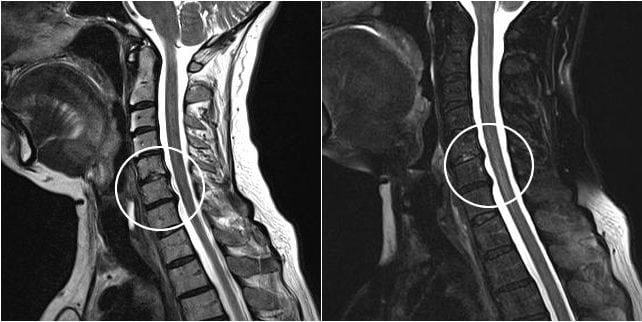

- рентгенография позвоночного столба и легких;

- КТ или МРТ;

Если терапевт, а именно к нему часто обращаются пациенты с кашлем, не обнаружил признаков инфицирования и присутствия посторонних предметов, то он проводит дальнейшее обследование больного. Обычно в таких случаях причиной становится или прием определенных препаратов для снижения артериального давления (Эналаприл, Лизиноприл), или остеохондроз. Диагностировать последний позволяет изучение рентгенографических изображений.

На них хорошо визуализированы истончившиеся межпозвонковые диски, сместившиеся позвонки, разросшиеся края костных пластинок. Пациент направляется для дальнейшего лечения к вертебрологу или неврологу.